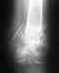

Моему сыну, год назад в результате травмы(перелом обеих костей голени),был установлен стержень Санатметал (Sanatmetal).Он учится на машиниста в железнодорожном техникуме,последний курс. При прохождении профосмотра, хирург его не допускает к практике по причине электропроводимости стержня Санатметал. Можно ли работать машинистам, не доставая стержень?И к кому обратиться за помощью?